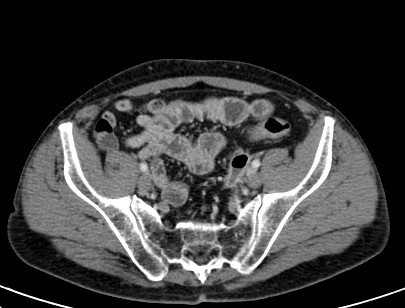

TC ABDOMEN: Se confirman los hallazgos vistos en ecografía. Se aprecia un engrosamiento mural > 4mm de un segmento aproximado de 5.5 cm de longitud con infiltración de la grasa adyacente y sin visualizar colecciones ni gas extraluminal, hallazgos compatibles con diverticulitis aguda no complicada.

CONCLUSIÓN: Diverticulitis aguda no complicada. HINCHEY grado 0